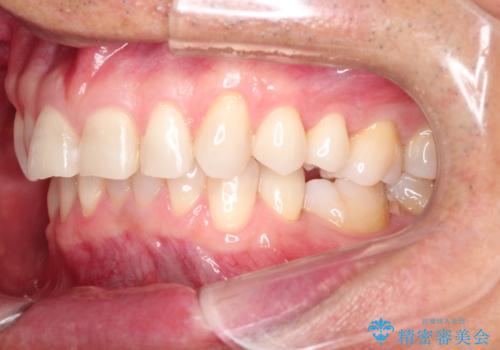

上の前歯の隙間とがたつきをインビザラインできれいな歯並びへ

- 以前矯正治療を他院にて行っており、最近上顎の隙間とガタガタが気になるとのことで来院されました。

上顎のみインビザラインにて矯正治療を行うこととなりました。

使用時間を守っていただけたので、比較的スムーズに矯正を終了することができました。